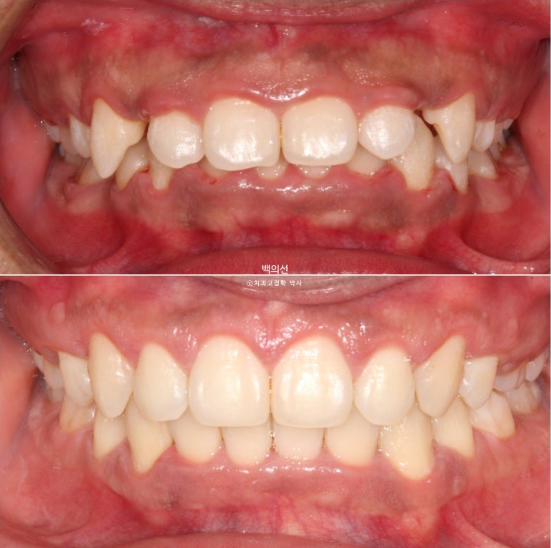

사진은 브라켓을 뗀 후 사진이고, 위 앞니가 아랫니를 많이 덮는 과개교합이 보입니다.

아랫니가 안 보일 정도의 심한 과개교합 입니다.

클리피씨 브라켓을 뗀 후 잇몸성형 직후 사진입니다.

잇몸성형 일주일 후 잇몸이 잘 아물었습니다.

이제 전후 비교 보겠습니다.

중심선은 잘 맞으며 과개교합은 좋아졌습니다.

안모에서는 확실한 거미스마일 개선이 눈에 띕니다.